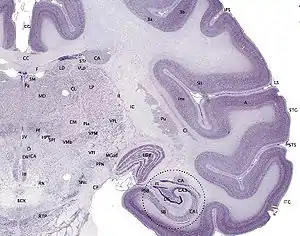

Cerebral cortex

The cerebral cortex is typically described as comprising three parts: the sensory, motor, and association areas. These sensory areas receive and process information from the senses. The senses of vision, audition, and touch are served by the primary visual cortex, the primary auditory cortex, and primary somatosensory cortex. The cerebellar cortex is the thin gray surface layer of the cerebellum, consisting of an outer molecular layer or stratum moleculare, a single layer of Purkinje cells (the ganglionic layer), and an inner granular layer or stratum granulosum. The cortex is the outer surface of the cerebrum and is composed of gray matter.[1]

The motor areas are located in both hemispheres of the cerebral cortex. Two areas of the cortex are commonly referred to as motor: the primary motor cortex, which executes voluntary movements, and; the supplementary motor areas and premotor cortex, which select voluntary movements. In addition, motor functions have been attributed to: the posterior parietal cortex, which guides voluntary movements, and; the dorsolateral prefrontal cortex, which decides which voluntary movements to make according to higher-order instructions, rules, and self-generated thoughts.